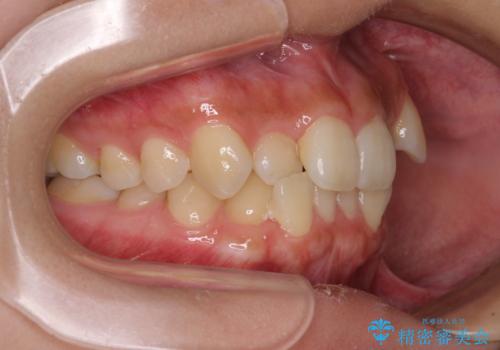

奥歯の咬み合わせが理想的であり、歯の移動に時間のかかる出っ歯でもなかったため、2年程度で治療を終えることを目標としましたが、無事に予定通りの2年間で終えることができました。

- 上下前歯のデコボコと八重歯を気にして来院された患者様です。

叢生を解消する際に出っ歯とならないようにするために、上下左右の小臼歯計4本を抜歯することとしました。